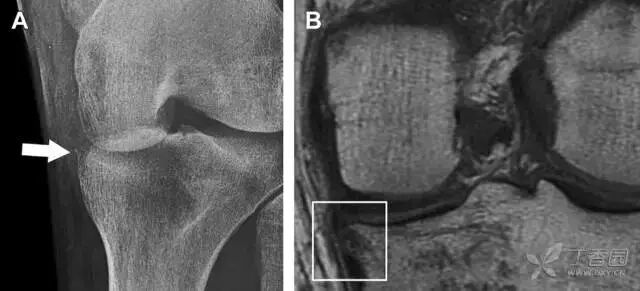

11Segond 骨折

Segond 骨折是发生在胫骨平台外侧的垂直撕脱性骨折(图 4)。这种骨折在前后位 X 线片上显示最佳。

屈曲位时膝关节受到内旋暴力作用,导致皮质骨撕脱性骨折,这种骨折常发生在运动员身上。常引起股骨内髁和胫骨平台后内侧骨挫伤,75%~100% 的患者伴前交叉韧带断裂,33% 的患者伴外侧半月板损伤。

图 4 一位足球运动员的 Segond 骨折

A 正位片示关节线下方胫骨外侧皮质撕脱(箭头)。B MRI 冠状位 T1 加权像示附着于髂胫带的骨折碎片(空箭头)。